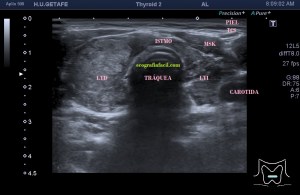

Era un nódulo hiperecogénico en el contexto de la tiroiditis en el estudio de una ecografía tiroidea.

Te enseño las imágenes, típicas de una exploración tiroidea de protocolo con semiología de tiroiditis.

De la imagen 1 a 7 el protocolo habitual, el estudio particular del nódulo con medidas y aplicación del doppler demuestra el aspecto típico del Caballero Blanco.

De la 8 a la 11 estudio con Doppler.

La imagen 12 y 13 están adquiridas con una sonda de 18 Mhz.

En la 14 un ganglio reactivo con medidas respetadas.

El el 15 tienes un vídeo de un corte axial de El Caballero Blanco.

Resumen de las imágenes que has visto en el caso de hoy:

1. Hipoecogenicidad del parénquima

2. Heteroecogenicidad

3. Múltiples nódulos hipoecoicos muy pequeños

4. Doppler Color y Doppler Power aumentado de tamaño en el nódulo

Este es el aspecto ecográfico descrito anteriormente de la patología que habitualmente puede albergar el nódulo del que trata hoy el post y que no es otra que la de la Tiroiditis de Hashimoto.

El Caballero blanco, recibe el nombre debido a su semiología hiperecogénica, homogénea y solitaria circunscrito en la patología referida con anterioridad, puede aparecer en esta patología de forma benigna o degenerar en otro tipo de patología a formas malignas como el linfoma tiroideo.